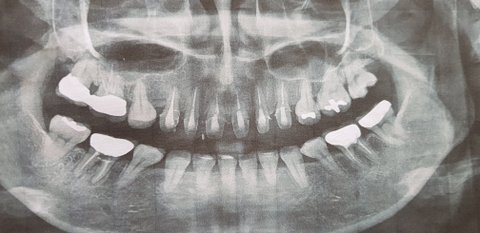

1, 3월27일 치아미백과 앞이사이 떨어진 레진을 붙이려고 동네치과에 감. 사진 찍어 보더만 상담실장 따라가서 설명들으라고.... 상담실장 왈 내이는 치아미백이 안되는 치아라고 함. 그리고 이럴때는 치아성형을 해야하며, 하고난뒤 만족감에 대하여서만 계속 권유 받음. 어떻게 하냐니 앞이 6개를 살짝갈고 씌우는 것이라 이야기들음. 망설이다 6×700.000=4.200.000 에 200.000만원 깍아준다하여 뭐에 씌인듯 계약함. 그리고 글씃이가 지갑을 통체로 잊어먹어서 돈을 한꺼번에 주지 못한다고 하니, 현금으로 나누어 내라고 하여, 남편에게 현금 100만원 받아서 줌

4, 4월20일 계속적인 신경치료와 앞이 다듬는 과정중, 보지 못했던 내 앞이 6개를 얼핏보고 충격받음

계약과 다르게 진행되고, 얼핏본 치아상태 내가잘못봤나 싶어서, 다른치과에 가서 의치를 빼고, 내 이빨을 보고 통곡을 했음. 앞이 6개가 쌀알갱이 처럼 남기고 다 깎였음. 그리고 내가하는 것이 무엇인지 정확하게 설명들음. 너무 어이없고, 사기 당했다는 생각에 치과로 전화를 함. 상담실장이 전화받아서 이때까지 이야기 한거랑 전혀다른 이야기를 들음. 내 앞이 6개가 모두 레진으로 덮여 있어서 다 갈아내야 했고, 가격이 다른치과와 너무 다르다고 항의한 나에게, 자기치과는 고 퀄티의 기술을 지니고 있어서 하고난뒤 가격에 비하여 만족할것이라고만 답변하며, 앞이는 부르는게 값이라는 말만 들음, 그리고 23일 예약도 잡혀있으니 그날와서 이아기 하자고 해서 알았다고 함